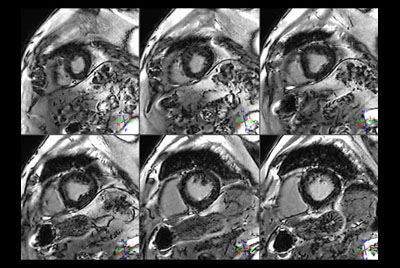

Cardiac infarction with Compressed SENSE

Cardiac infarction with fat-free mDIXON imaging

Cardiac imaging with Compressed SENSE

Acute myocardial infarction

30 minute Cardiac Function and Fibrosis at 1.5T

30 minute Cardiac Function and Fibrosis at 3.0T